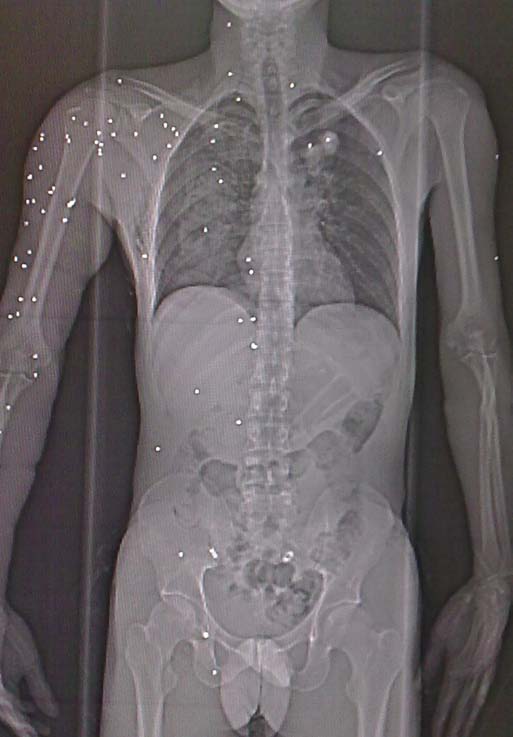

s the blast injuries are deliberately devised to inflict maximum damage, these injuries often occur in crowded places like markets and the range of people effected varies greatly as regards age, sex, number of people injured .We present a case of an young individual who received more than 75 pellet injuries that were scattered throughout the body. Most of the pellets were received on the right upper limb with a few in chest, abdomen and pelvis. The neck fortunately had pellets in safe areas .This was one rare case of trauma in which so many pellets were received by a single patient. In this patient the vitals were Normal. Neurological examination was normal as was Orthopaedic examination with evidence of bleeding from multiple sites on the body which was taken care of during the initial assessment. However there was no serious source of bleeding. Trauma in Kashmir valley has taken a toll. Many people have died, some have got lifelong disabilities and some are incapacitated. Neck: The area of the neck is especially Important as this area is unprotected by bone or dense muscular covering. The most significant neck injuries result from penetrating trauma, blunt neck trauma does occur and can be particularly difficult to manage because it often involves the airway, the first priority in trauma care. Fatality rates for penetrating neck trauma range up to 50% for rifle or shotgun blasts.